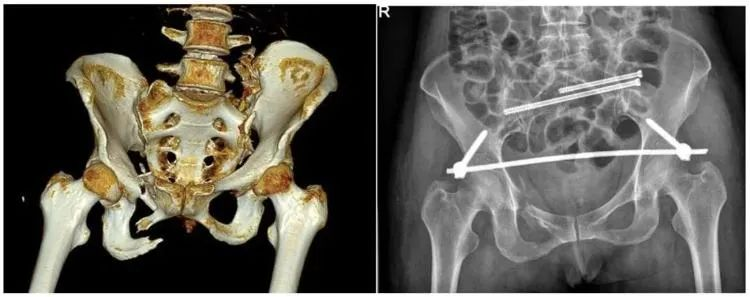

【医疗科普】:稳定性骨折影像

稳定性骨折

【医疗科普】:不稳定性骨折影像

不稳定性骨折

二、稳定性骨折&不稳定性骨折

另外,我们根据骨盆骨折是否稳定可以分为稳定性的骨折和不稳定性的骨折。如果是不稳定性的骨折医生可能会建议病人进行手术治疗,把不稳定性的骨折变成稳定性的骨折。